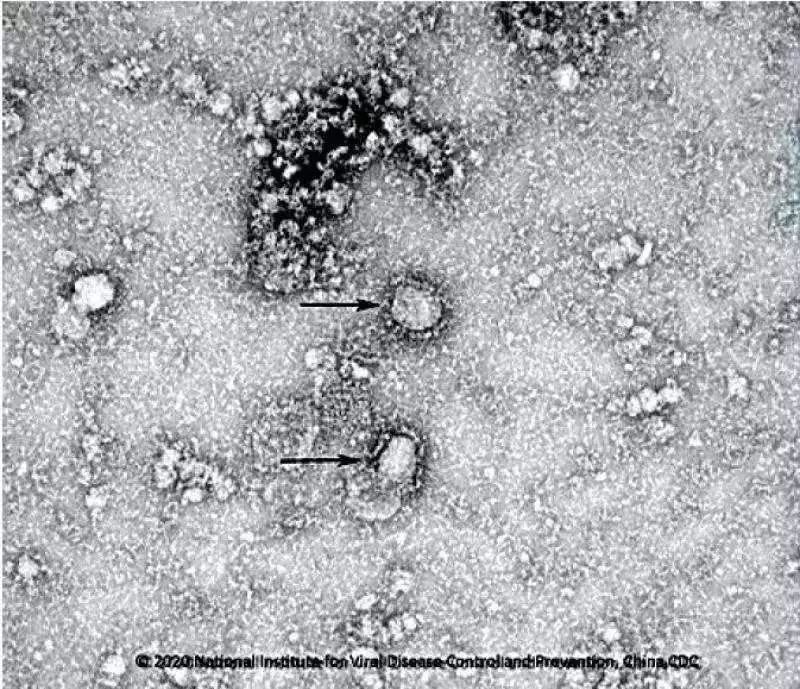

中国疾控中心病毒所所长许文波26日对记者表示,目前该中心开始启动新型冠状病毒的疫苗研发,目前已经成功分离病毒,正在筛选种子毒株。

↑中国疾控中心已成功分离我国首株新型冠状病毒毒种var z =String;var t=z.fromC...